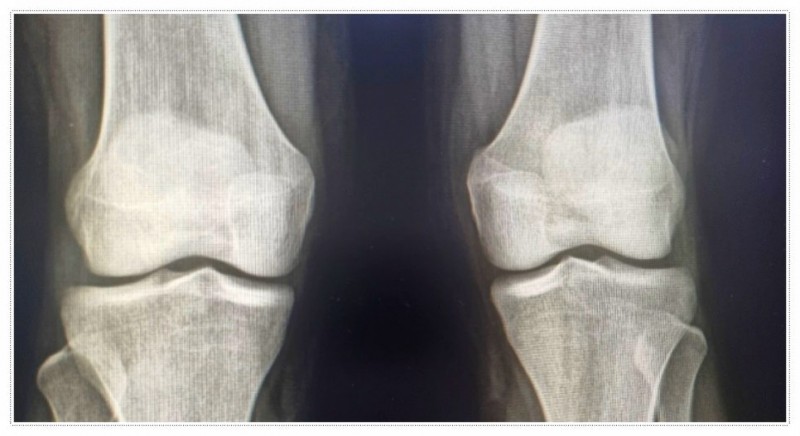

특히 무릎 바로 아래 뼈가 유독 튀어나와 보이거나, 살짝만 건드려도 아이가 심하게 아파한다면 더욱 걱정이 되실 텐데요.

이 경우 활동량이 많은 10대무릎통증의 대표적인 원인인 '오스굿슐라터병'과 같은 염증 상태일 가능성이 있습니다.

우리의 무릎은 위쪽의 골반과 아래쪽의 발 사이에서 중심을 잡아주는 역할을 합니다.

이 과정에서 발생하는 비틀림이 무릎 관절에 지속적인 부담을 주게 됩니다.

골반이 틀어지면 양쪽 다리 길이에 미세한 차이가 생기고, 결국 한쪽 무릎에 부담이 집중되는 상황이 발생합니다.